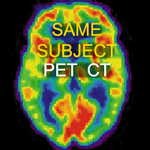

The Same Subject PET/CT collection contains cases of registering a PET or CT dataset with an MRI or CT.